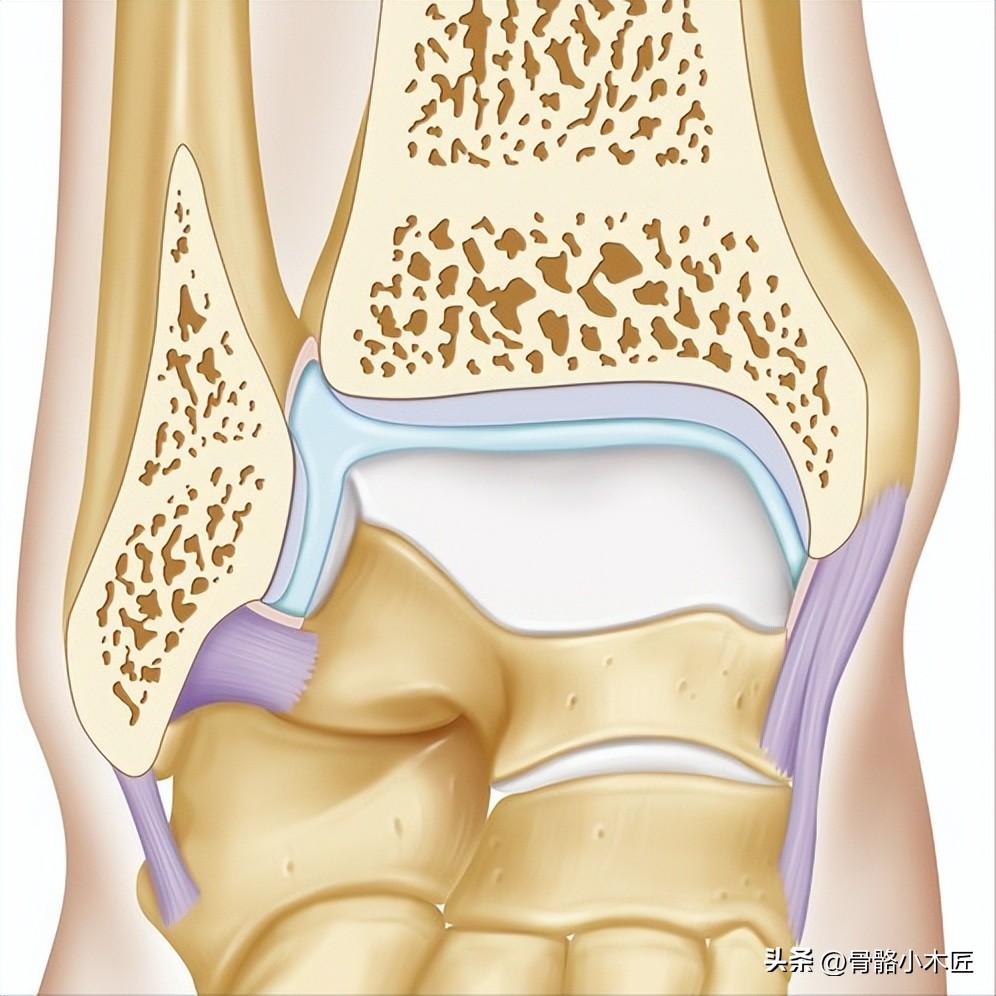

踝关节有胫骨远端,腓骨远端和距骨体构成,胫骨远端内侧凸出部分为内踝,后缘呈唇状突起为后踝,腓骨远端突出部分为外踝;内踝外踝和胫骨远端关节面构成踝穴,包容距骨体,距骨呈前宽后窄,使踝关节背屈时候与踝穴适应性好;踝关节是人体负重的重要关节之一,负重中期,关节面承受的压力约为体重的2倍,负重后期约为体重的5倍,这也是踝关节容易受伤,容易发生退变的原因之一。

正常情况下,以足外缘与小腿垂直为中立位0°,踝关节有背屈20°-30°,跖屈45°-50°,内翻30°,外翻30-35°的活动度,在踝关节跖屈时,距骨与踝穴间隙增大,使踝关节相对不稳,这时容易发生损伤。